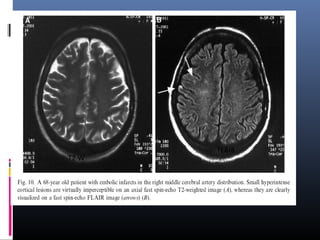

 Embolic infarcts- Improved visualization

 Chronic infarctions- typically dark with a rim of high signal. Bright peripheral zone

corresponds to gliosis, which is well seen on FLAIR and may be used to

distinguish old lacunar infarcts from dilated perivascular spaces.

T2 W

FLAIR